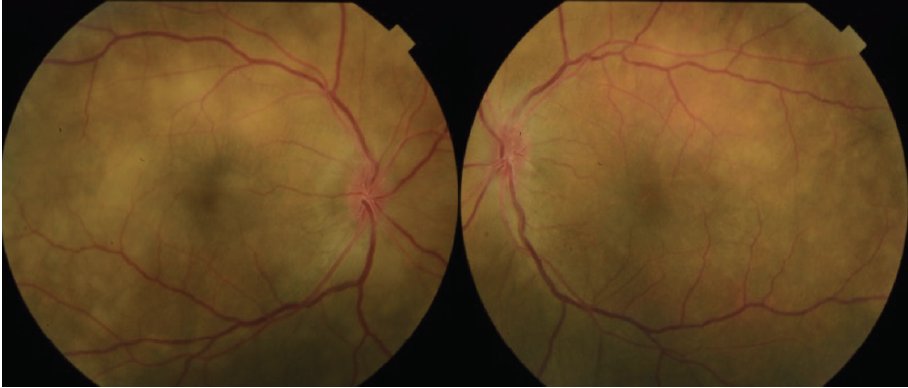

Dilated fundus examination revealed clear media without inflammation OU and numerous deep, discrete, and patchy yellow lesions throughout the posterior pole with irregular borders and multiple areas of distinct retinal elevation OU (Figure 1). The optic nerves were noted to be hyperemic OU without significant elevation, hemorrhage, or obscuration of vessels. Of note, there was no evidence of peripheral pathology or retinal vasculitis. OCT imaging showed numerous areas of intraretinal and subretinal fluid pockets of varying size with notable retinal and choroidal undulation through the macula (Figure 2). Fluorescein angiography showed multiple irregular patchy and pinpoint areas of hyperfluorescent foci throughout the posterior pole with leakage and distinct pockets of pooling in the later frames (Figure 3).

Figure 1. Color fundus photography on presentation shows numerous subretinal discrete yellow lesions throughout the posterior pole with irregular borders and multiple areas of distinct retinal elevation OU.